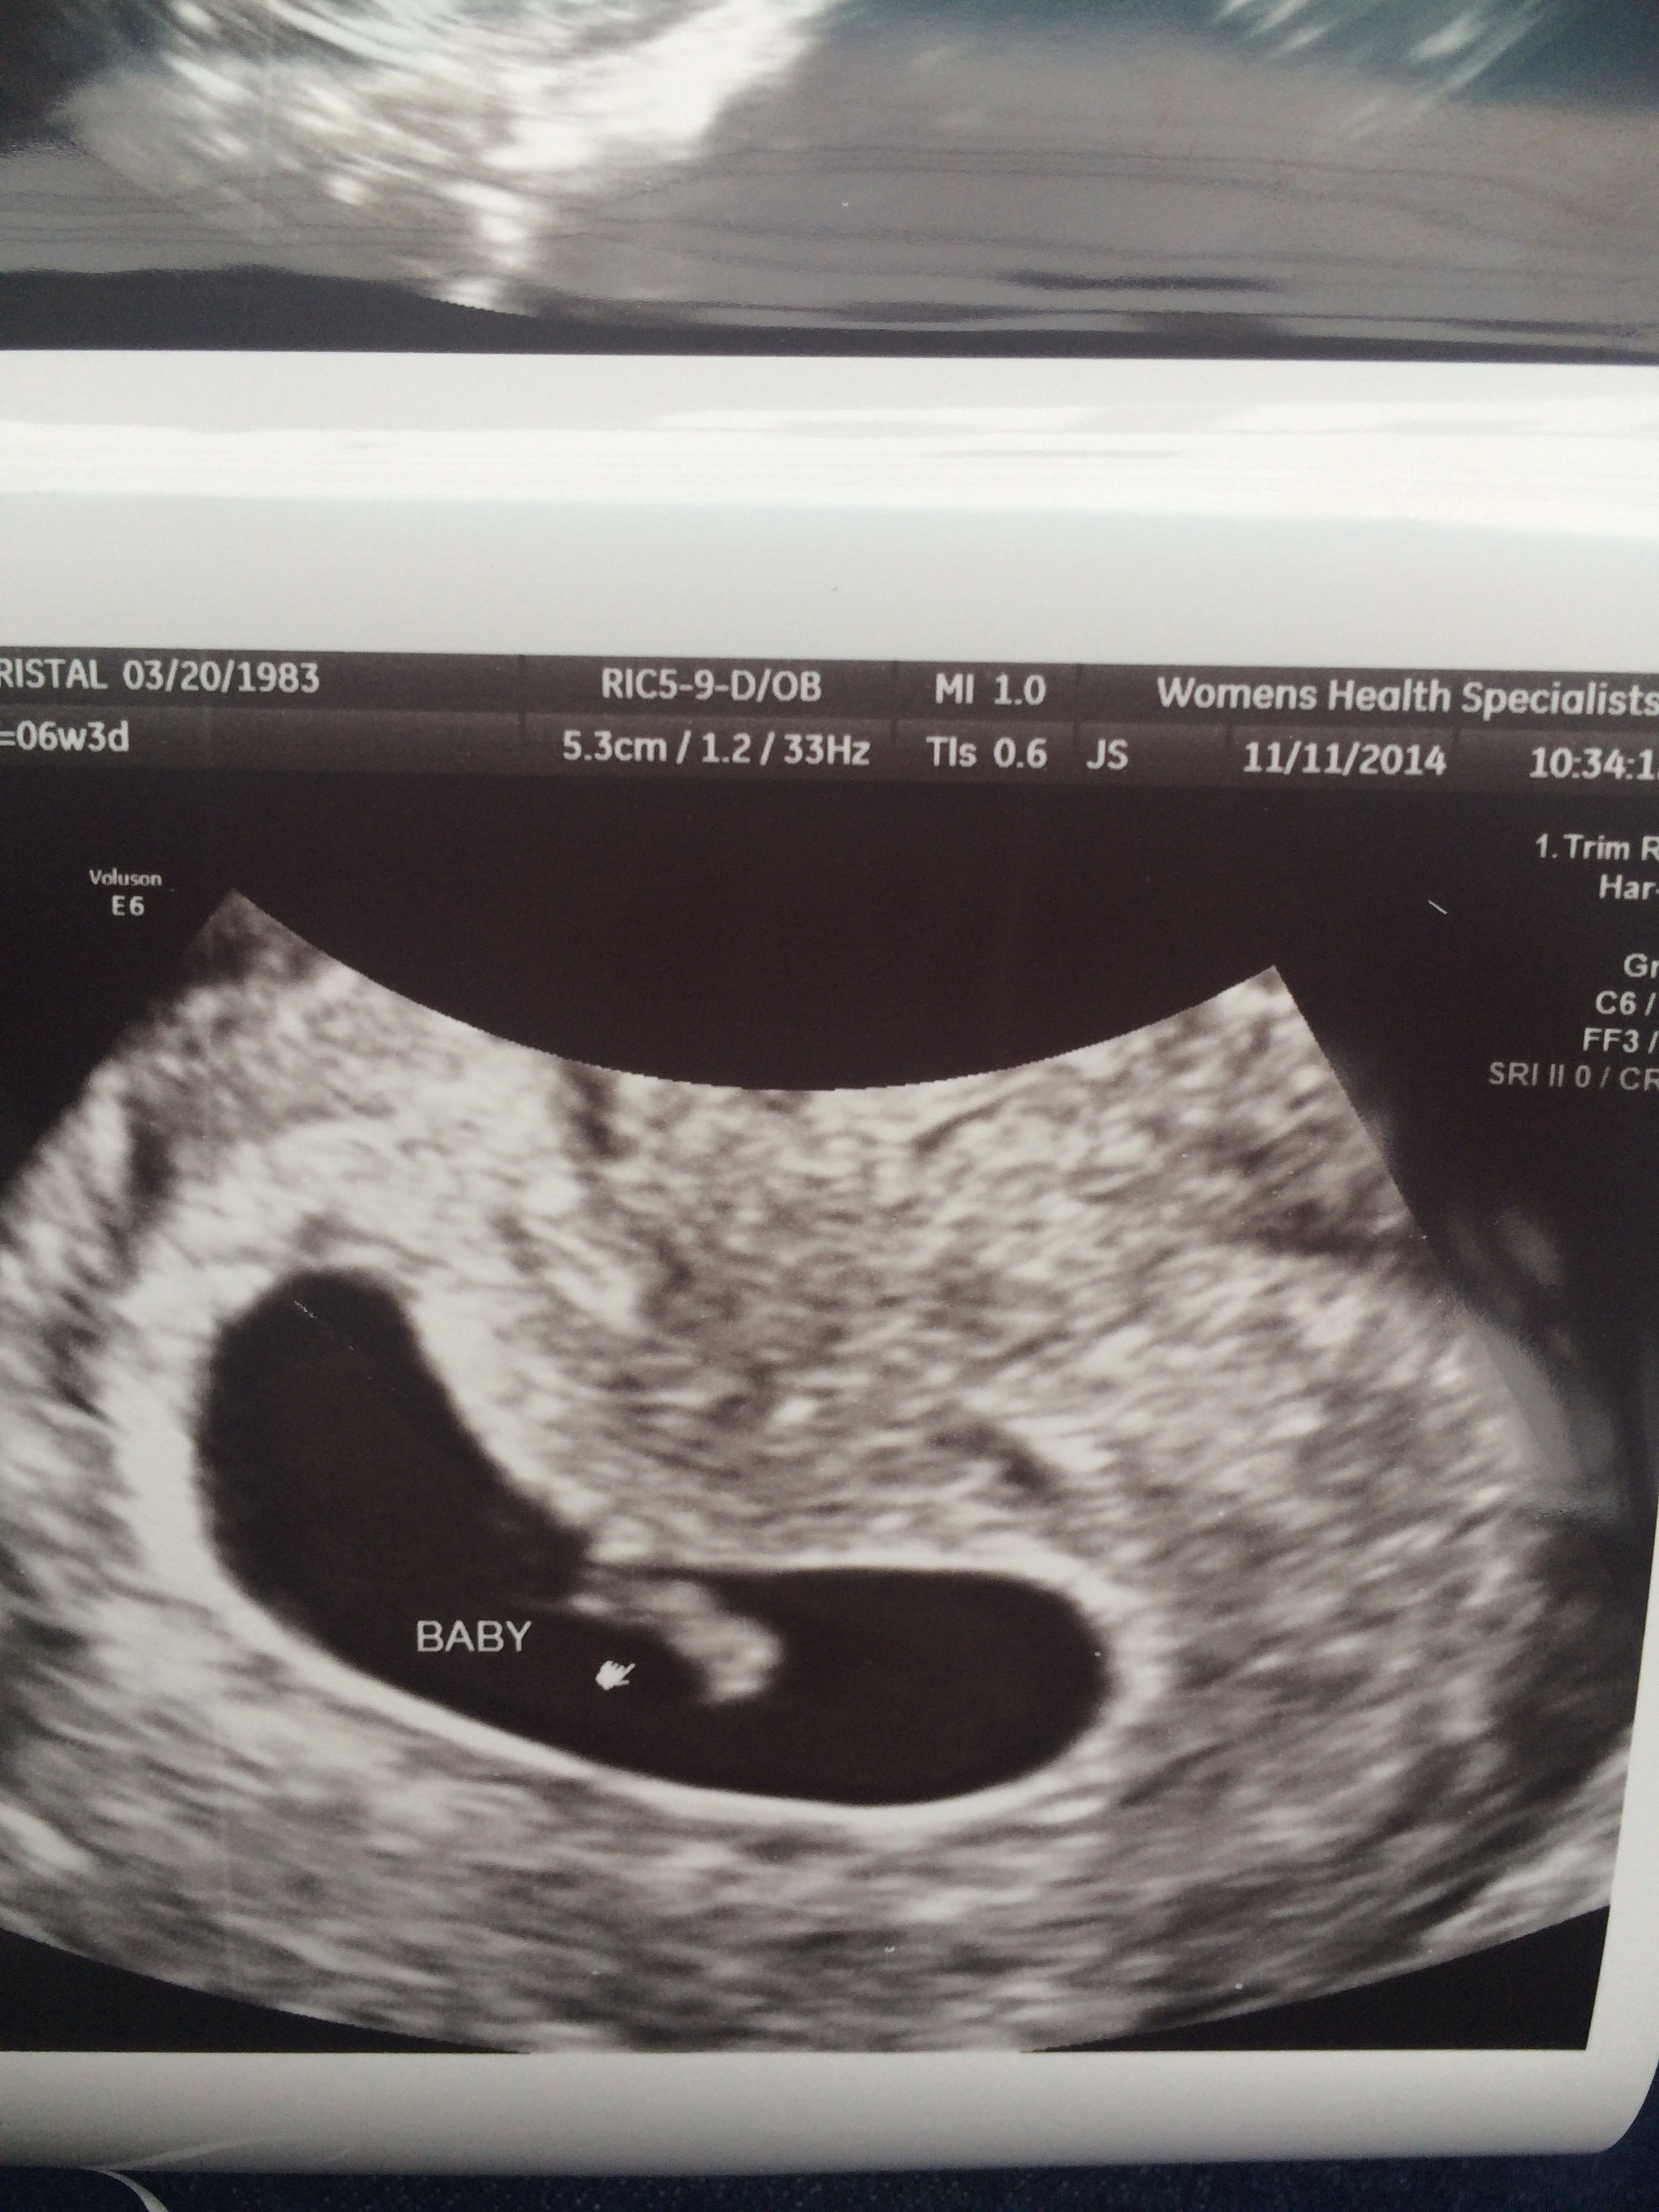

Had our first Prenatal appt. today. Here is what you may see at 6 wks!

• here's mine at 6 weeks 0 days yours is much better quality congratulations that's so exciting I got to see the heartbeat did you I'm curious as to what your BPM's were